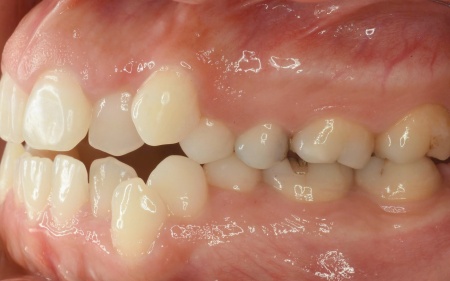

拝見したところ、奥歯で噛んだ際に上下の前歯が触れ合わず、隙間ができている状態でした。

これは開咬(かいこう)と呼ばれ、前歯で食べ物を噛み切るのが難しい噛み合わせです。

加えて全体的に歯が重なり合ってデコボコに生えており、歯磨きがしにくく、審美性にも悪影響がでています。

また、骨格的には下顎が後下方に位置しており、お顔全体が縦に長いタイプでした。